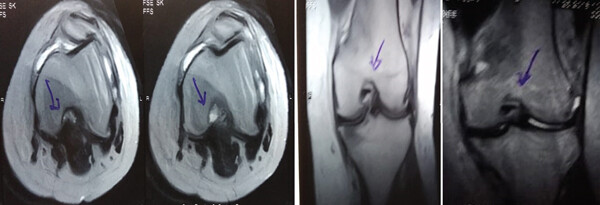

MRI:治療前后的MRI結(jié)果

治療前后的MRI結(jié)果

治療前 MRI 顯示內(nèi)側(cè)和外側(cè)半月板后角 III 級(jí)撕裂。

治療后MRI檢查顯示內(nèi)側(cè)和外側(cè)半月板后角撕裂有所改善?;颊甙Y狀改善,日常生活活動(dòng)能力增強(qiáng)。

結(jié)論:間充質(zhì)干細(xì)胞治療后,MRI檢查顯示內(nèi)側(cè)和外側(cè)半月板后角撕裂有所改善 ,關(guān)節(jié)功能也有改善,未出現(xiàn)嚴(yán)重不良事件。可以達(dá)到干細(xì)胞治療半月板損傷短期療效的目標(biāo)。